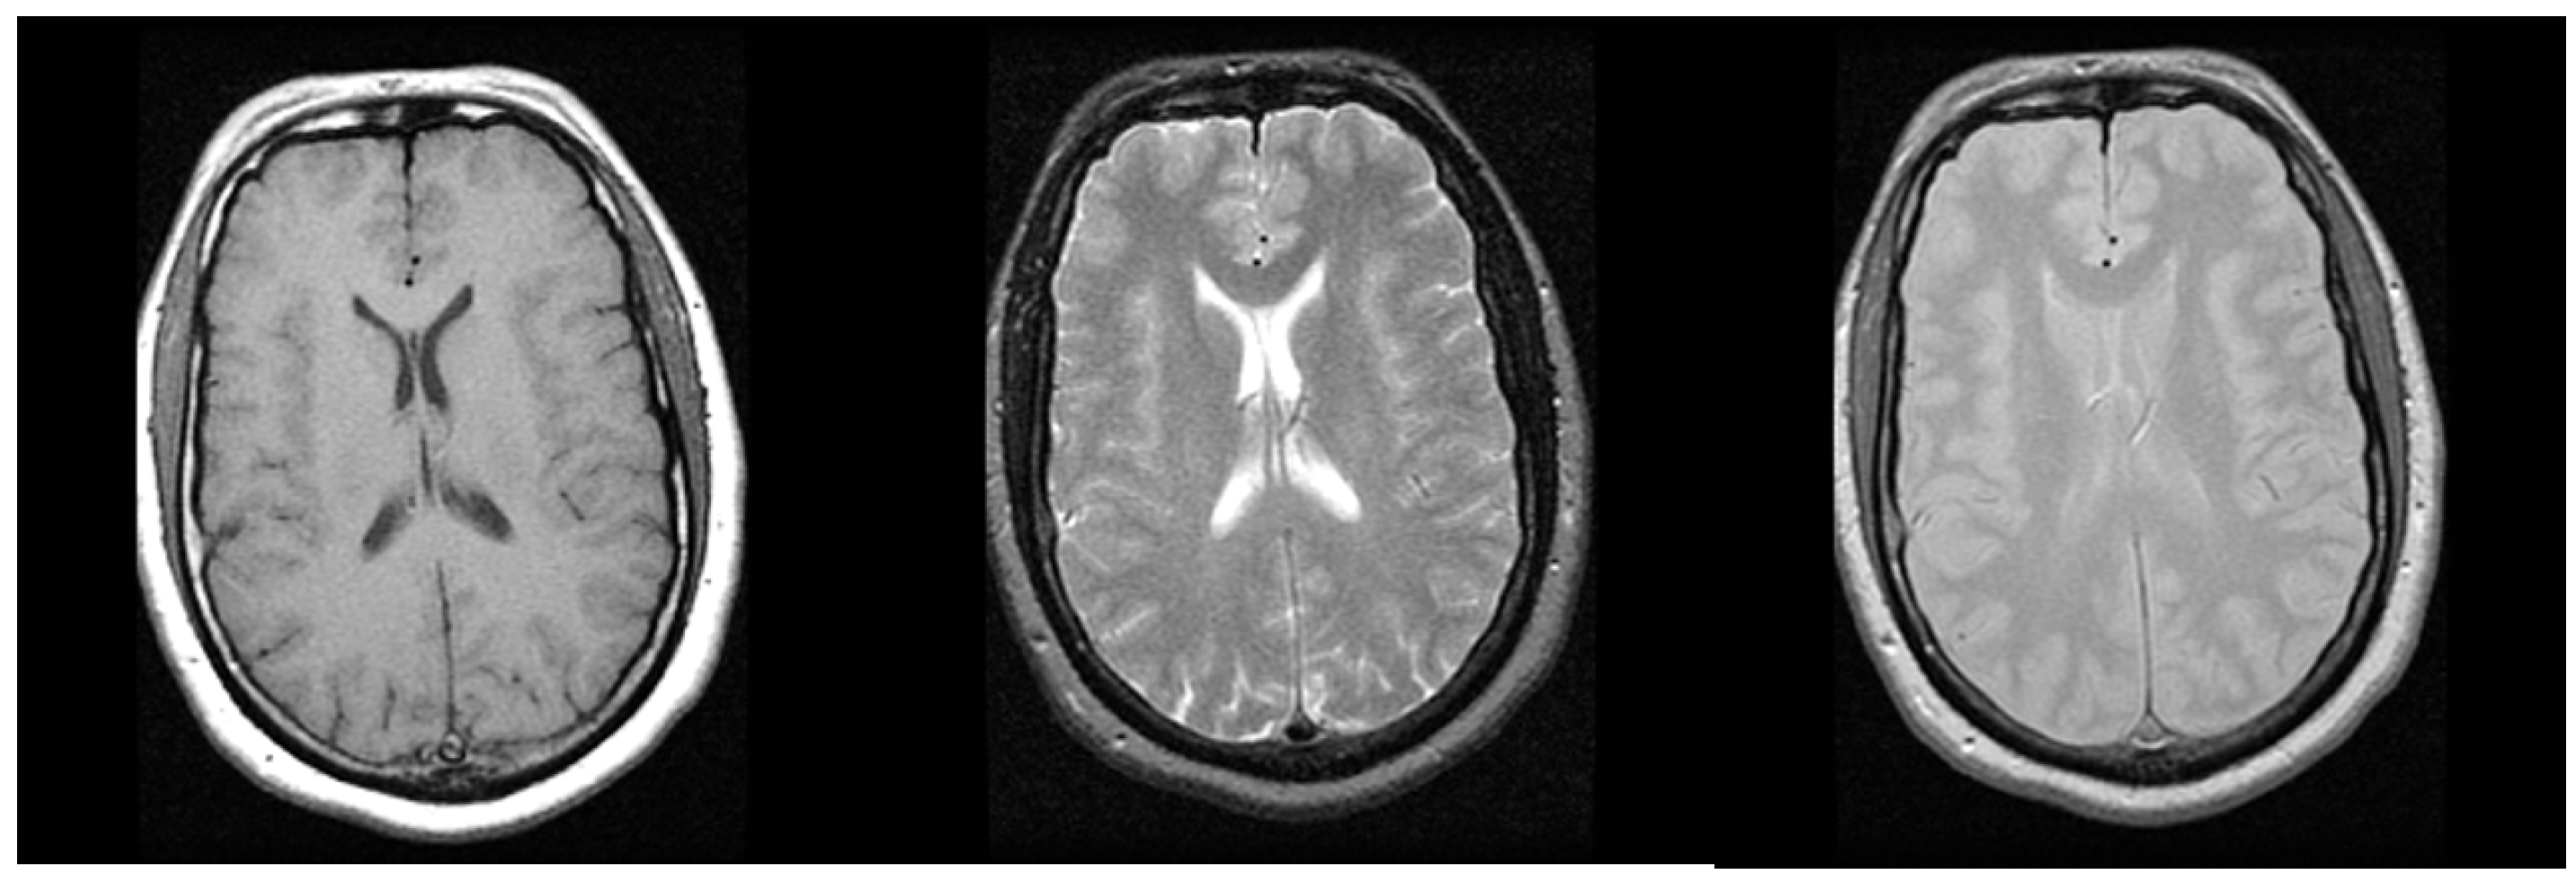

2.2. Magnetic Resonance Imaging

| Brain | (512, 512, 200, -) | 12–16 bits | 100 MB | |

| TCGA-BRCA | MR Mammography | (256, 256, 148–160) | 12 |

| TCGA-GBM | MR T2 Flair Axial | (384, 512, 25–29) | 12 |

| MR T2 Flair Axial | JPEG-LS | 2.75 ± 0.2267 |

| Lossless JPEG-XR | 2.85 ± 0.2206 | |

| Lossless JPEG2000 | 2.91 ± 0.2463 | |

| HEVC AI | 2.26 ± 0.1818 | |

| HEVC RA | 2.51 ± 0.1955 | |